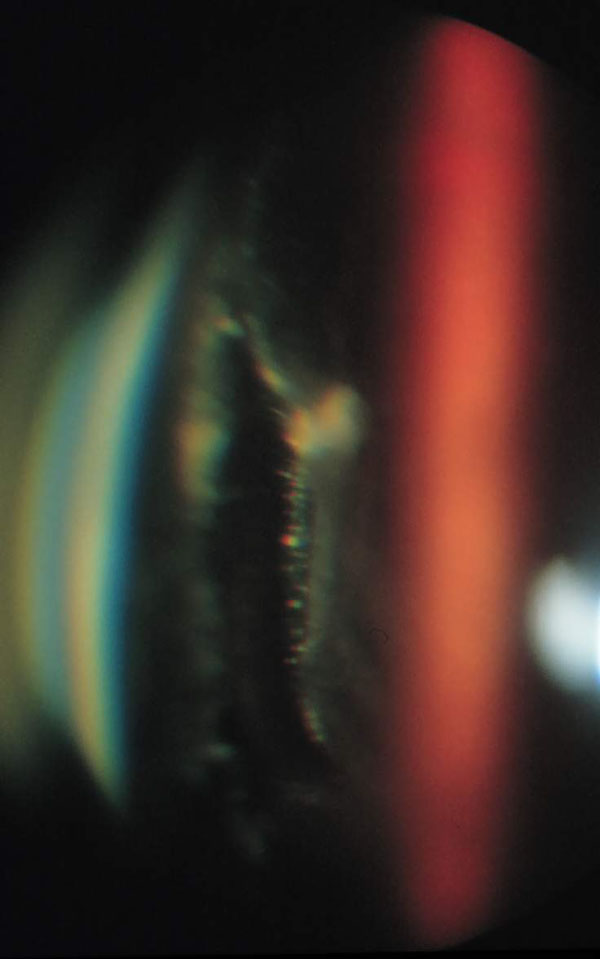

34. ábra

34. ábra Ablatio retinae ellen végzett bedomborító műtét után macular pucker alakult ki. A réslámpás biomikroszkópos felvételen részleges hátsó üvegtesti leválás, az epiretinális membán széléhez kapcsolódó hátsó üvegtesti felszín figyelhető meg.